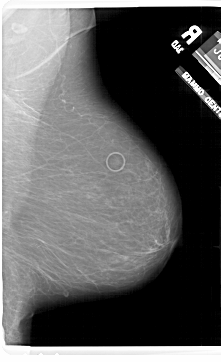

A_1802_1.RIGHT_MLO

RIGHT_CC LINES 6301 PIXELS_PER_LINE 3661 BITS_PER_PIXEL 12 RESOLUTION 43.5 NON_OVERLAY

RIGHT_MLO LINES 6871 PIXELS_PER_LINE 4186 BITS_PER_PIXEL 12 RESOLUTION 43.5 NON_OVERLAY